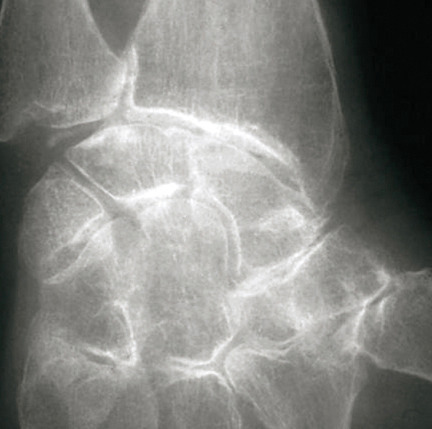

La forme pseudorhumatoïde est rare (5 %), simulant une polyarthrite rhumatoïde. L’arthrite chronique à PPC se présente comme une oligo- ou une polyarthrite, avec parfois des signes systémiques d’inflammation (élévation de la vitesse de sédimentation et de la protéine C-réactive [CRP]). La superposition d’accès aigus microcristallins est évocatrice de ce diagnostic. Il s’agit d’un diagnostic différentiel de polyarthrite rhumatoïde du sujet âgé ou de pseudopolyarthrite rhizomélique. Le diagnostic repose sur la mise en évidence des cristaux de PPC, même si les radiographies standard sont évocatrices. L’atteinte radiographique associe des calcifications des cartilages articulaires (fig. 7) et des fibrocartilages (fig. 8, 9, 10 et 11) [à rechercher systématiquement sur les radiographies de poignets, genoux et symphyse pubienne]. La mise en évidence d’une chondrocalcinose sur des radiographies standard renforce le diagnostic de rhumatisme à PPC mais l’absence de dépôts calciques ne l’élimine pas (la sensibilité de la radiographie standard étant imparfaite). L’échographie peut mettre en évidence des dépôts de PPC, qui apparaissent comme une fine bande hyperéchogène au sein des cartilages hyalins et comme des points scintillants dans les fibrocartilages ou dans la membrane synoviale. La sensibilité de l’échographie est bien supérieure à celle de la radiographie standard. Le scanner peut également mettre en évidence des dépôts calciques évocateurs, notamment au niveau du rachis ou du bassin qui sont plus difficilement explorés par les radiographies et l’échographie.

Les arthropathies liées à l’arthrose ou destructrices ont une fréquence qui augmente avec l’âge. L’arthrose associée aux dépôts de PPC touche en particulier les genoux, avec une symptomatologie chronique et/ou des accès aigus cristallins. Par comparaison avec l’arthrose idiopathique, l’arthrose avec dépôt de PPC serait à l’origine d’une symptomatologie plus inflammatoire, toucherait des articulations inhabituelles (radiocarpienne, carpienne, gléno-humérale, médio-pied et arrière-pied, cheville) et serait associée à plus d’ostéophytes et de géodes. Cette arthropathie dégénérative peut s’accompagner de lésions structurales sévères avec disparition rapide de l’interligne (arthropathies destructrices : hanches, genoux, poignets, coudes) mimant une ostéo­arthropathie nerveuse.